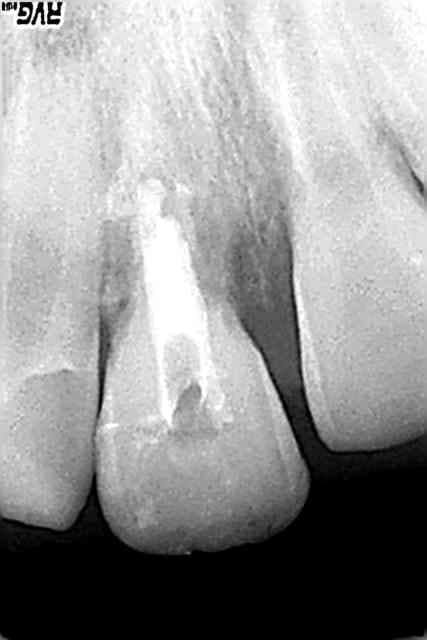

22/08/2007 à 21h07

à un an

âge de l'enfant : 9ans

la rhyzalyse de 11 semble bloquée par le ttt au MTA,ouf!(angle prévu incessamment sous peu ne vs inquiétez pas)

12 répond aux tests

mais...

21:

au froid,il a une sensation de chaleur...?

apex tjours pas fermé

qd faut y aller,faut y aller,à cette apexification?

ou je remets un cierge ?(ou autre incantation ou prière: si qq'un a qqe chose qui marche,je suis preneuse :je deteste tenter d'induire une fermeture apicale aléatoire)